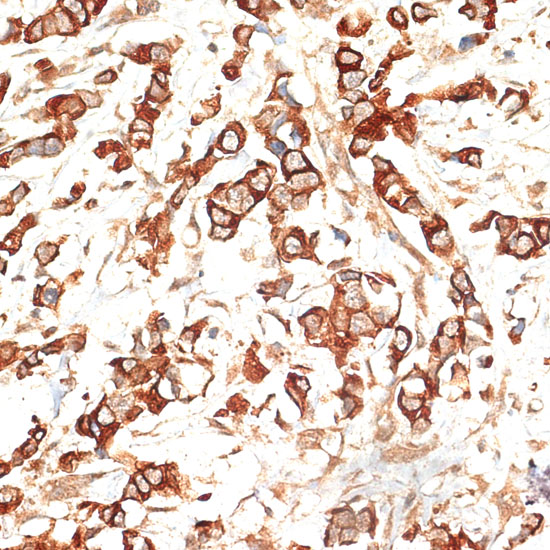

Immunohistochemistry of paraffin-embedded human breast cancer using KRT13 at dilution of 1:100 (40x lens).